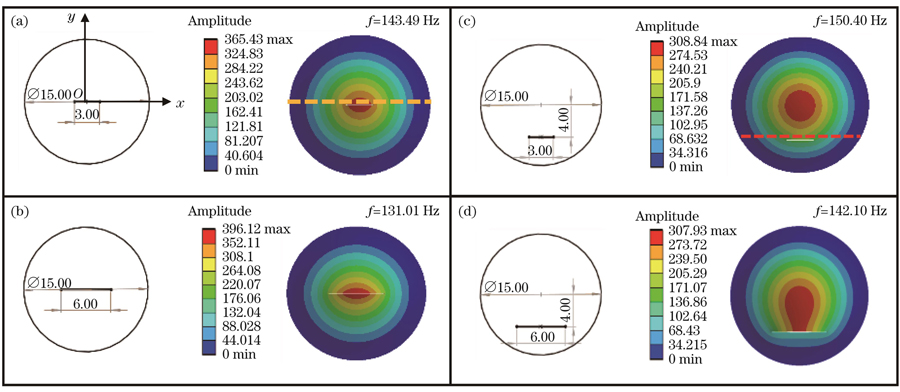

如

图 5. 划伤薄膜一阶振动模态的仿真结果。(a)中心3 mm划伤薄膜;(b)中心6 mm划伤薄膜;(c)偏心3 mm划伤薄膜;(d)偏心6 mm划伤薄膜

Fig. 5. Simulation results of first-order vibration modes of scratched films. (a) Film with a 3 mm scratch in the center; (b) film with a 6 mm scratch in the center; (c) film with an eccentric 3 mm scratch; (d) film with an eccentric 6 mm scratch

图 6. 划伤薄膜振幅分布截面图。(a)中心划伤薄膜y=0.1处;(b)偏心划伤薄膜y=-3.7处

Fig. 6. Section of amplitude of scratched films. (a) Section at y=0.1 of the centrally scratched film; (b) section at y=-3.7 of the eccentrically scratched film

First, the theoretical analysis proves that using the spatial carrier phase extraction method to detect the amplitude distribution in eardrum samples in the vibration mode is reasonable. In the finite element simulation and experimental analysis, the vibration modes of the artificial eardrums with defects were analyzed, and the results showed that different defects affect the amplitude distribution in the first-order vibration mode for the eardrums differently. For the perforated eardrum samples, the amplitude distribution was analyzed by varying the size and location of the perforation. The results show that the amplitude near the perforation increases significantly with the increase in perforation size (Figs. 3 and 4), and an increase in the number of fringes is observed in the experimental results (Fig. 11). By changing the location of the perforation, the maximum amplitude shifts off-center with the perforation, and the larger the perforation, the more evident the deviation. The amplitude distribution for the scratched eardrum samples was analyzed by varying the size and location of the scratch. The results show that at the same location, the larger the scratch length, the larger the surface amplitude of the film (Fig. 5), and the amplitude changes more significantly near the scratch location (Fig. 6). The experimental results show an increase in the number of fringes, and the shape of the fringe near the central scratch is flat (Fig. 12). When the scratch is off-center, the effect on the amplitude near the scratch is significantly greater than that at the center. The amplitude distribution for the calcified eardrum samples was analyzed by varying the thickness of the calcified layer (Fig. 7). The amplitude of the film decreases with an increase in the thickness of the calcified layer but is more evident at the location of the calcified layer (Figs. 8 and 13).